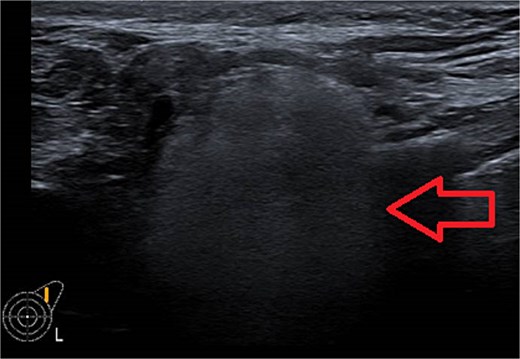

Ultrasound of left breast and axilla: Revealed rupture of the left implant with intracapsular and extracapsular leakage, along with echogenic peri-implant fluid. Enlarged axillary lymph nodes were visualized (Figs 1 and 2).

Ultrasound of the left axilla showed the typical appearance of the lymph node siliconoma.